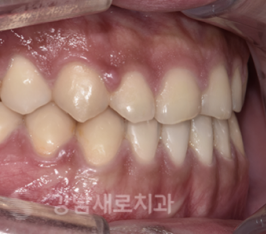

선 수술후 비발치 주걱턱 교정 전/후

또한, 골격의 부조화가 해결된 상태에서

교정 치료를 시작하기 때문에

치아 교정의 결과를 더 정확하게

예측할 수 있어 그만큼 완성도를

높인 치료를 기대할 수 있다고 했어요.

또한 준비 교정이 생략되면서

교정 기간 또한 적어도

6개월 이상 단축할 수 있으며,

뿐만 아니라 수술 후 얼굴 뼈가 치유되는

기간 동안 치아 또한 이동이 이루어지기

때문에 더 빠르게 치료가 가능하여

양악전 교정에 비해 치료 기간이 짧다는

장점이 존재한다고 말했어요.

선수술교정 전/후